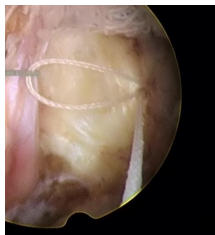

一次性纖維環(huán)縫合器的臨床應(yīng)用:

隨著纖維環(huán)縫合器縫合纖維環(huán)技術(shù)的推廣,很多學(xué)者做了相關(guān)的臨床研究。Parker等對(duì)30例纖維環(huán)縫合患者進(jìn)行了2年隨訪研究,零復(fù)發(fā)且椎間隙高度無(wú)改變。Bailey等通過(guò)對(duì)750名患者對(duì)比研究,發(fā)現(xiàn)纖維環(huán)非縫合組在術(shù)后2年時(shí)的再手術(shù)率較縫合組高45%。研究發(fā)現(xiàn),縫合纖維環(huán)可提高椎間盤(pán)生物力學(xué)性能,縮短其愈合時(shí)間,同時(shí)也減緩椎間盤(pán)組織的退變進(jìn)程。修復(fù)后纖維環(huán)回縮可減少對(duì)神經(jīng)根刺激,可有效消除疼痛癥狀。目前LDH髓核摘除術(shù)后復(fù)發(fā)的主要病因?yàn)槔w維環(huán)缺損、持續(xù)重復(fù)應(yīng)力因素等,比較明確的病因?yàn)槭中g(shù)導(dǎo)致的纖維環(huán)缺損,總結(jié)得出髓核突出少、纖維環(huán)缺損嚴(yán)重者術(shù)后的復(fù)發(fā)率高??p合后纖維細(xì)胞受到反復(fù)牽拉應(yīng)力刺激,可促進(jìn)纖維環(huán)的愈合和防止炎癥因子的產(chǎn)生。纖維環(huán)愈合產(chǎn)生的瘢痕組織可減輕關(guān)節(jié)突關(guān)節(jié)的應(yīng)力作用??p合纖維環(huán)可提高術(shù)后髓核“再水化”,促進(jìn)腰椎功能恢復(fù)。纖維環(huán)縫合益處:閉合裂口;降低術(shù)后復(fù)發(fā)率及再手術(shù)率;減輕髓核組織的免疫學(xué)反應(yīng)和炎癥介質(zhì)的外滲;有利于髓核的再生修復(fù)。要點(diǎn):切口大小以5mm的線形縱切口較佳,8mm以上需平行或交叉縫合2針;縫合針距離邊緣2~3mm為宜;縫合前,應(yīng)行邊緣探查,尋求無(wú)佳的縫合點(diǎn)。目前纖維環(huán)縫合面臨的重要問(wèn)題是如何改善或降低縫合處的應(yīng)力積累,受應(yīng)力積累影響瘢痕組織及神經(jīng)纖維可能侵入椎間盤(pán),可引起盤(pán)源性疼痛。有學(xué)者對(duì)比研究得出,單針簡(jiǎn)單縫合,可降低術(shù)后復(fù)發(fā)率,雙針交叉或平行縫合療效更好,而改良荷包縫合,術(shù)后能避免髓核再次突出,生物力學(xué)完整性可得到更好保留。